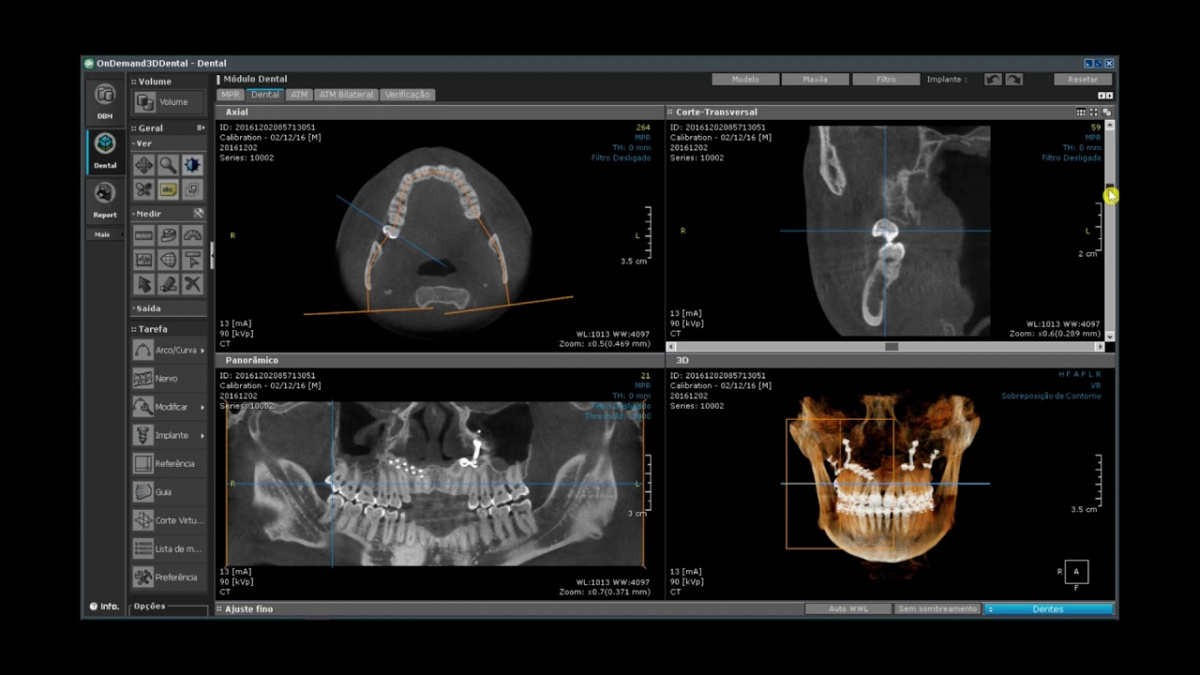

Немаловажным, а может главным вопросом, является универсальность программы-просмотровщика, в которой будут работать врачи-стоматологи. У Papaya 3D есть два варианта программ: Triana и OnDemand3D. Оба просмотровщика обладают схожим интерфейсом и имеют самые важные опции, а именно:

Таким образом обе программы являются простыми в пользовании, но обладающими обширным спектром возможностей для диагностики любыми специалистами-стоматологами. В данные программы происходит загрузка классических файлов DICOM 3.0, которые являются общепринятым форматом записи данных пациента. Это важный момент, так как позволяют врачу, имеющему полную версию программы загружать даже сторонние исследования и просматривать их в этих программах. Простота в освоении этих программ позволяет даже специалисту, не работающему раннее с этими программами, быстро адаптироваться и получить качественную информацию. Возможность выгрузки STL-файла дополнительно создает возможность интегрировать данные с цифровым ортопедическим протоколом.